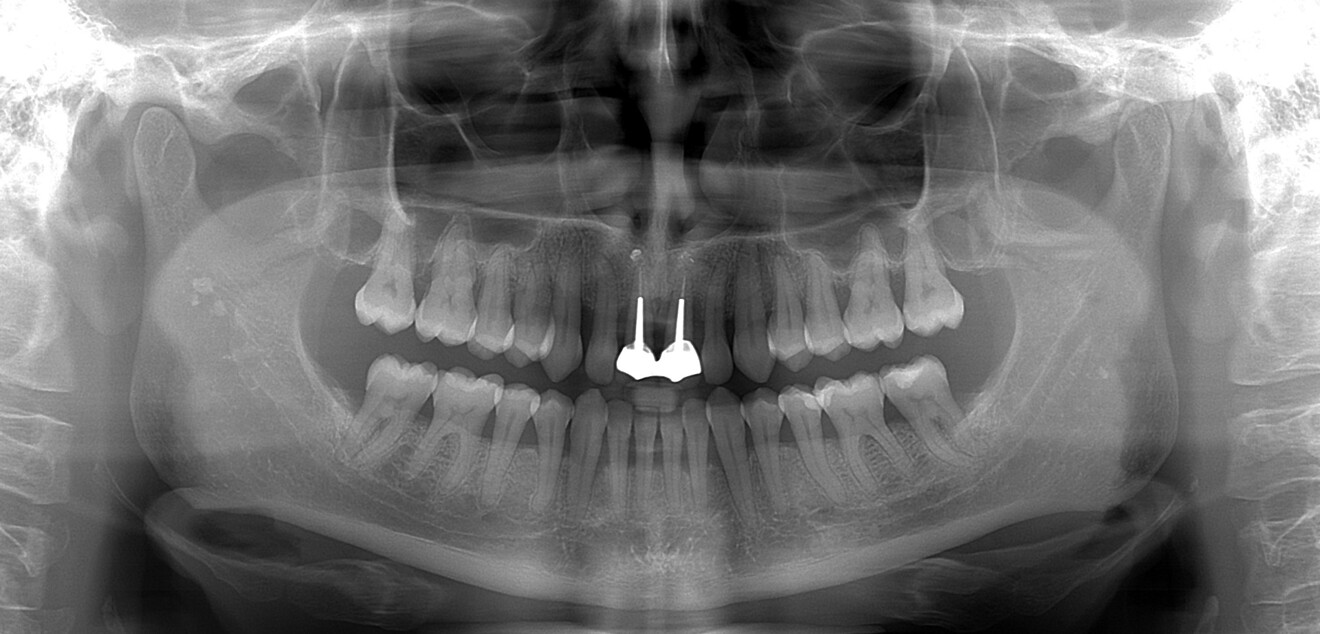

Il s’agit d’une patiente de 48 ans adressée en 2020 par l’un de nos confrères. Ancienne fumeuse, sans problèmes médicaux particuliers, cette patiente présente un long historique parodontal qui, associé à des lésions endodontiques sur 11 et 21, aboutissent à la perte de ses deux incisives centrales (Fig. 7). Cette patiente, active, ne s’est pas fait traiter plus tôt par crainte d’une longue période de temporisation avec une prothèse amovible.

À l’examen la patiente présente en vestibulaire, au niveau de 11 et 21, des pertes de substances importantes (osseuses et gingivales), particulièrement en 21 avec la destruction de l’intégralité de la paroi vestibulaire de la crète, et une perte totale d’ancrage de la racine, ainsi qu’un frein labial inséré haut sur la crête. On conserve néanmoins l’architecture des tissus mous avec la présence de papilles interdentaires et un volume osseux apical suffisant pour permettre l’ancrage des implants (Figs. 8–10). L’enjeux du traitement est de réaliser les extractions, de poser les implants, de reconstruire la crête osseuse, et de mettre en place des provisoires fixes sur les implants, en conservant l’architecture des tissus mous.